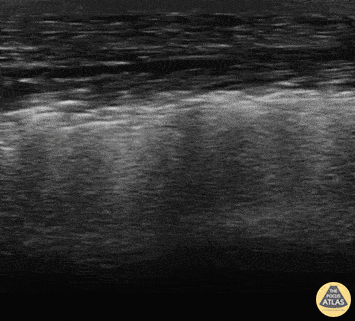

Middle-aged male who presented to the emergency department with fever and elbow pain, swelling and redness. Ultrasound placed over the soft tissue area showed dirty shadowing consistent with gas forming bacterial infection. Alexis Salerno, MD